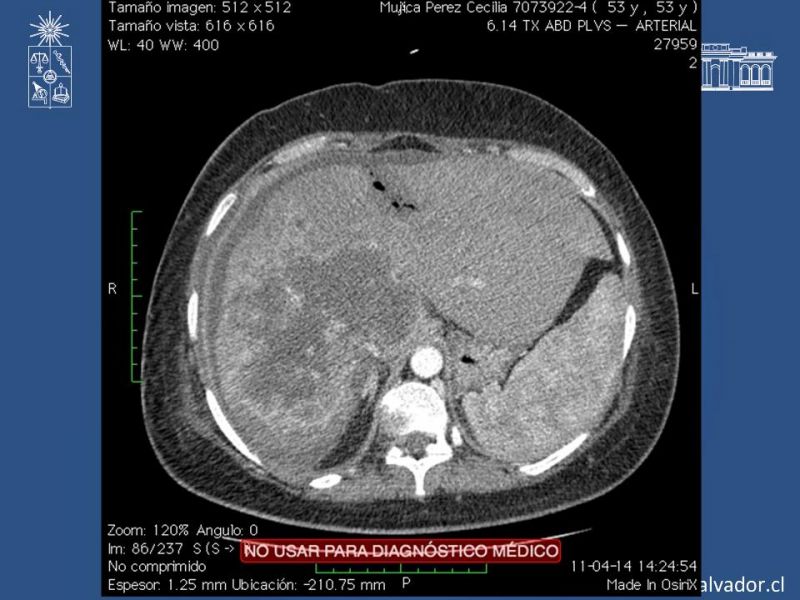

ALPPS: Associating Liver Partition with Portal Vein Ligation for Staged Hepatectomy

Especialidad: Hepatobiliopancreático | Autor: Dr. Daniel Calderón M.